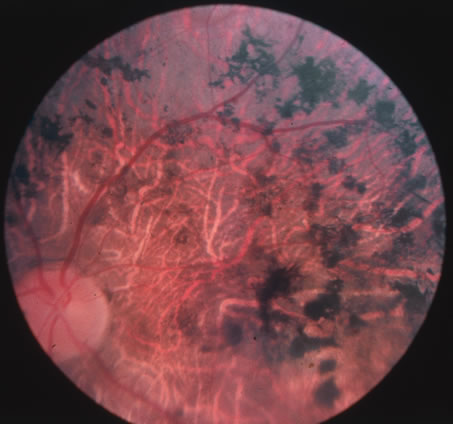

In primary ocular HSV infections, a severe follicular conjunctivitis with regional adenopathy is present. Vesicles may appear on the eyelid skin or lid margin, producing blepharitis (Fig. 3). Corneal involvement initially takes the form of a superficial punctate keratitis, which may progress to dendritic or geographic ulceration. Stromal infiltrates and uveitis are less common and relatively mild in primary disease. In uncomplicated cases, lesions usually heal completely in 2 to 3 weeks without scarring. Most cases of ocular HSV are recurrences. Recrudescent ocular herpes may take the form of dendritic or geographic ulcers, recurrent erosions, interstitial or disciform stromal keratitis, and anterior uveitis.3 HSV may also be an agent of retinitis and acute retinal necrosis (Fig. 4).

The acute retinal necrosis (ARN) syndrome is most often caused by the herpes zoster virus, although occasionally it may be a result of herpes simplex infection.12 It is typically described in healthy patients although association with immunosuppressed patients has also been described. Granular, nonhemorrhagic areas of retinal necrosis may be observed in the fundus, often rapidly coalescing with resulting blindness often caused by retinal detachment. There is often an associated vasculitis and vitritis. In immunocompromised patients VZV or HSV retinitis may also take the pattern of progressive outer retinal necrosis (PORN) (Fig. 6). PORN differs from ARN in that the former is multifocal, localized to the outer retina, and is less often associated with vasculitis and vitritis.